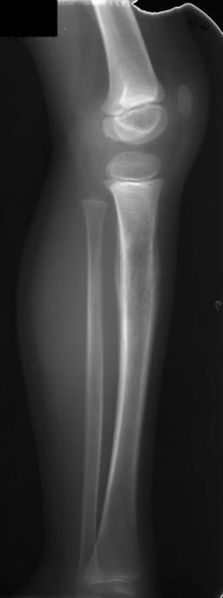

Xray small nodules generally up to 1 cm and variably sized cysts High resolution CT bronchiolocentric stellate nodules possibly with surrounding ground glass opacities, some with faint lucent cavity Advanced disease with cysts, emphysema adjacent to scarring, reticular and nodular opacities, honeycombing, can mimic IPF. Prolonged cholestasis was observed in 6 children with histiocytosis X Operative cholangiograms confirmed the patency of the extrahepatic biliary tree and showed marked distortion of intrahepatic bile ducts resembling that observed in sclerosing cholangitis Histologic examination showed portal fibrosis in all patients;. I Guerrieri Per Caso Gruppo di malati di istiocitosi a cellule di Langerhans e loro familiari, amici, sostenitori.

Xray small nodules generally up to 1 cm and variably sized cysts High resolution CT bronchiolocentric stellate nodules possibly with surrounding ground glass opacities, some with faint lucent cavity Advanced disease with cysts, emphysema adjacent to scarring, reticular and nodular opacities, honeycombing, can mimic IPF. Un progetto sull’istiocitosi a cellule di Langerhans e sindromi associate ha ricevuto un finanziamento europeo ed è sostenuto da 30 partecipanti tra i quali medici e rappresentanti di associazioni di pazienti con istiocitosi eurohistionet eurohistionet. Inoltre, le razze e le linee genetiche devono essere selezionate al fine di evitare malattie specifiche o problemi sanitari connessi con alcune razze e linee genetiche utilizzate nella produzione intensiva, quali ad esempio sindrome da stress dei suini, sindrome PSE (carni pallide, molli, essudative), morte improvvisa, aborto spontaneo, parti difficili che richiedono taglio cesareo.

Xray small nodules generally up to 1 cm and variably sized cysts High resolution CT bronchiolocentric stellate nodules possibly with surrounding ground glass opacities, some with faint lucent cavity Advanced disease with cysts, emphysema adjacent to scarring, reticular and nodular opacities, honeycombing, can mimic IPF. Histiocitosis X (HX) represents a group of disorders due to proliferation of abnormal histiocytes exhibiting immunophenotypical and ultrastructural features similar to Langerhans cells HX can become manifest as an isolated lesion or may affect several organs at once.